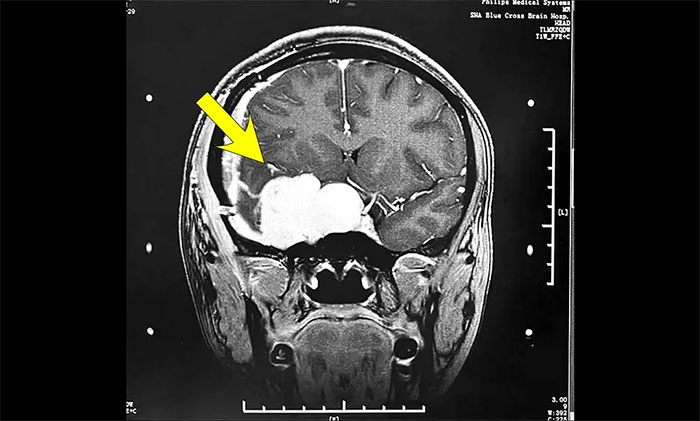

今年初醫(yī)院收治了一位女性患者。該患者因突發(fā)視力模糊,頭暈無法獨(dú)立行走,在外院檢查發(fā)現(xiàn)腦部右側(cè)鞍旁腫塊,手術(shù)病理診斷為海綿狀血管瘤。

▲ 入院時(shí)MRI檢查影像

腫瘤科(放療)頭部伽瑪?shù)督M陳琦主任完善檢查并開展多學(xué)科評估討論,其右側(cè)鞍旁海綿狀血管瘤與視神經(jīng)等重要結(jié)構(gòu)相鄰,若不及時(shí)干預(yù)治療,可因占位壓迫進(jìn)一步加重神經(jīng)功能障礙,甚至導(dǎo)致失明。而該部位病灶的手術(shù)治療難度高、風(fēng)險(xiǎn)大,術(shù)中可能對患者神經(jīng)功能造成嚴(yán)重?fù)p害,應(yīng)考慮采用創(chuàng)傷較小的伽瑪?shù)吨委煛?/p>